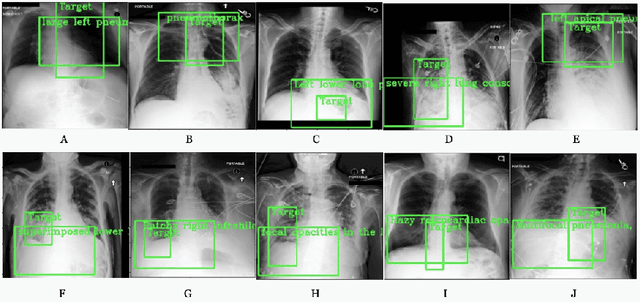

Detecting clinically relevant objects in medical images is a challenge despite large datasets due to the lack of detailed labels. To address the label issue, we utilize the scene-level labels with a detection architecture that incorporates natural language information. We present a challenging new set of radiologist paired bounding box and natural language annotations on the publicly available MIMIC-CXR dataset especially focussed on pneumonia and pneumothorax. Along with the dataset, we present a joint vision language weakly supervised transformer layer-selected one-stage dual head detection architecture (LITERATI) alongside strong baseline comparisons with class activation mapping (CAM), gradient CAM, and relevant implementations on the NIH ChestXray-14 and MIMIC-CXR dataset. Borrowing from advances in vision language architectures, the LITERATI method demonstrates joint image and referring expression (objects localized in the image using natural language) input for detection that scales in a purely weakly supervised fashion. The architectural modifications address three obstacles -- implementing a supervised vision and language detection method in a weakly supervised fashion, incorporating clinical referring expression natural language information, and generating high fidelity detections with map probabilities. Nevertheless, the challenging clinical nature of the radiologist annotations including subtle references, multi-instance specifications, and relatively verbose underlying medical reports, ensures the vision language detection task at scale remains stimulating for future investigation.